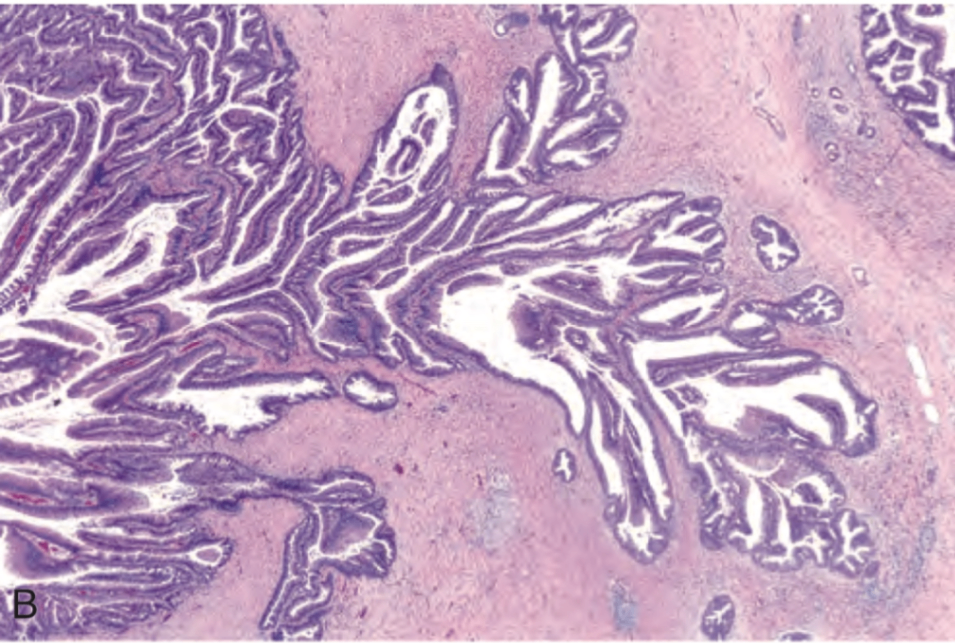

4. 관내 유두상 점액종양 (Intraductal papillary mucinous neoplasm, IPMN)

췌장 도관을 따라 발생하는 점액 생성 유두상 종양

- 췌장의 main duct에서 주로 발생

침윤성 암으로 진행 가능

• 낭종처럼 보이나 본질적으로는 췌장 도관 확장이 병태적 기전

• Mucinous cystic neoplasm과 구별되는 두 가지 핵심 소견:

- ovarian-type stroma 없음

- 췌장 도관 침범

• KRAS mutation이 약 80%에서 관찰되며, GNAS mutation이 특히 main duct IPMN에서 흔함

• 침윤성 암으로 진행될 때 TP53, SMAD4 mutation 관찰됨

Robbins and Cotran Pathologic Basis of Disease, 10e, pg 890